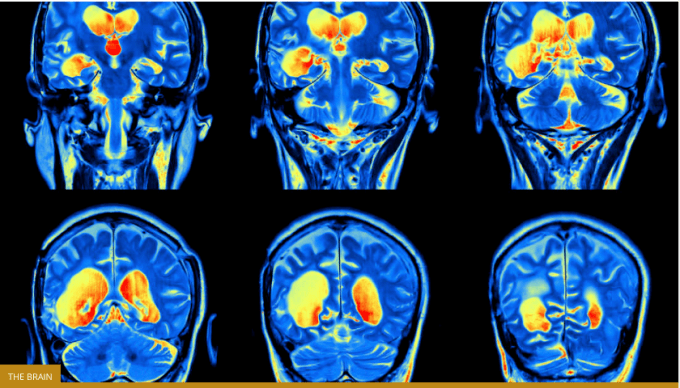

“The human medial (reward-related, OFC13) and lateral (non-reward-related, OFC47/12) orbitofrontal cortex networks that show different functional connectivity in patients with depression.” University of Warwick

This imaging technique was able to show activity in the connections between different parts of the human brain affected by depression, namely the medial and lateral orbitofrontal cortex. The lateral orbitofrontal cortex, associated with non-reward, showed considerably stronger connectivity in those in the depressive group.

As the team notes, the lateral orbitofrontal cortex is also connected with the area that is associated with one’s sense of self. Stronger connections were found between these two areas in those suffering from depression, perhaps explaining why people with depression often have thoughts of personal loss and low self-esteem.